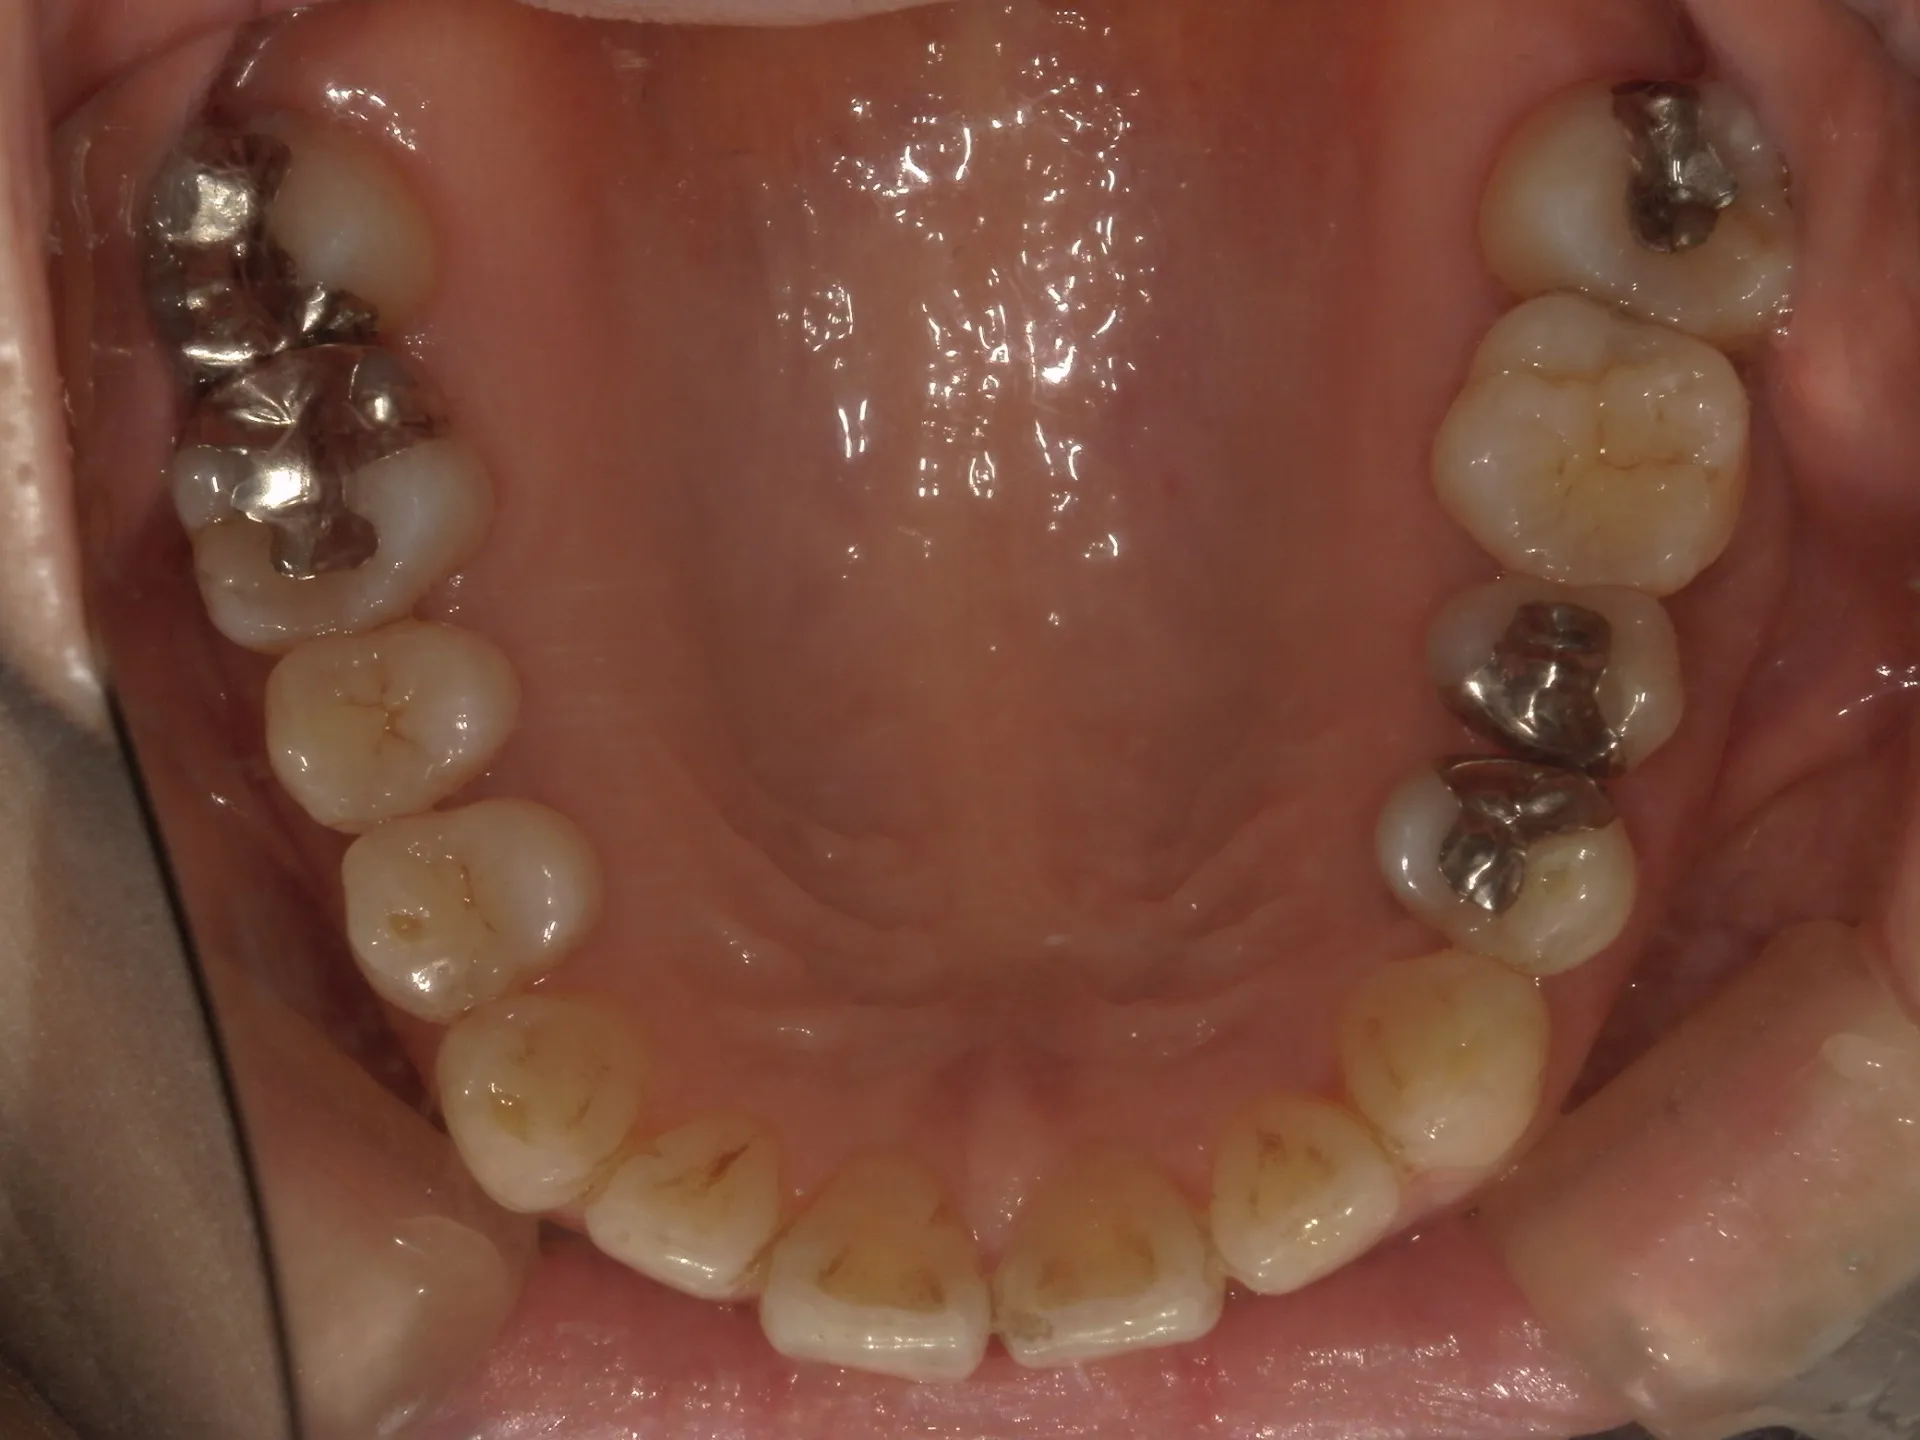

当院では矯正治療と歯周治療を平行して行うことにより矯正治療を進めていけることができました。

しかしながら、今回の治療途中で歯茎が腫れるなどの影響もあり、歯周治療中の矯正治療はリスクであることは患者様にも初回の段階で説明していることもあり、患者様もこの状態の歯並びで満足しており、歯を残すためにも今回は矯正治療を中断する希望をされました。